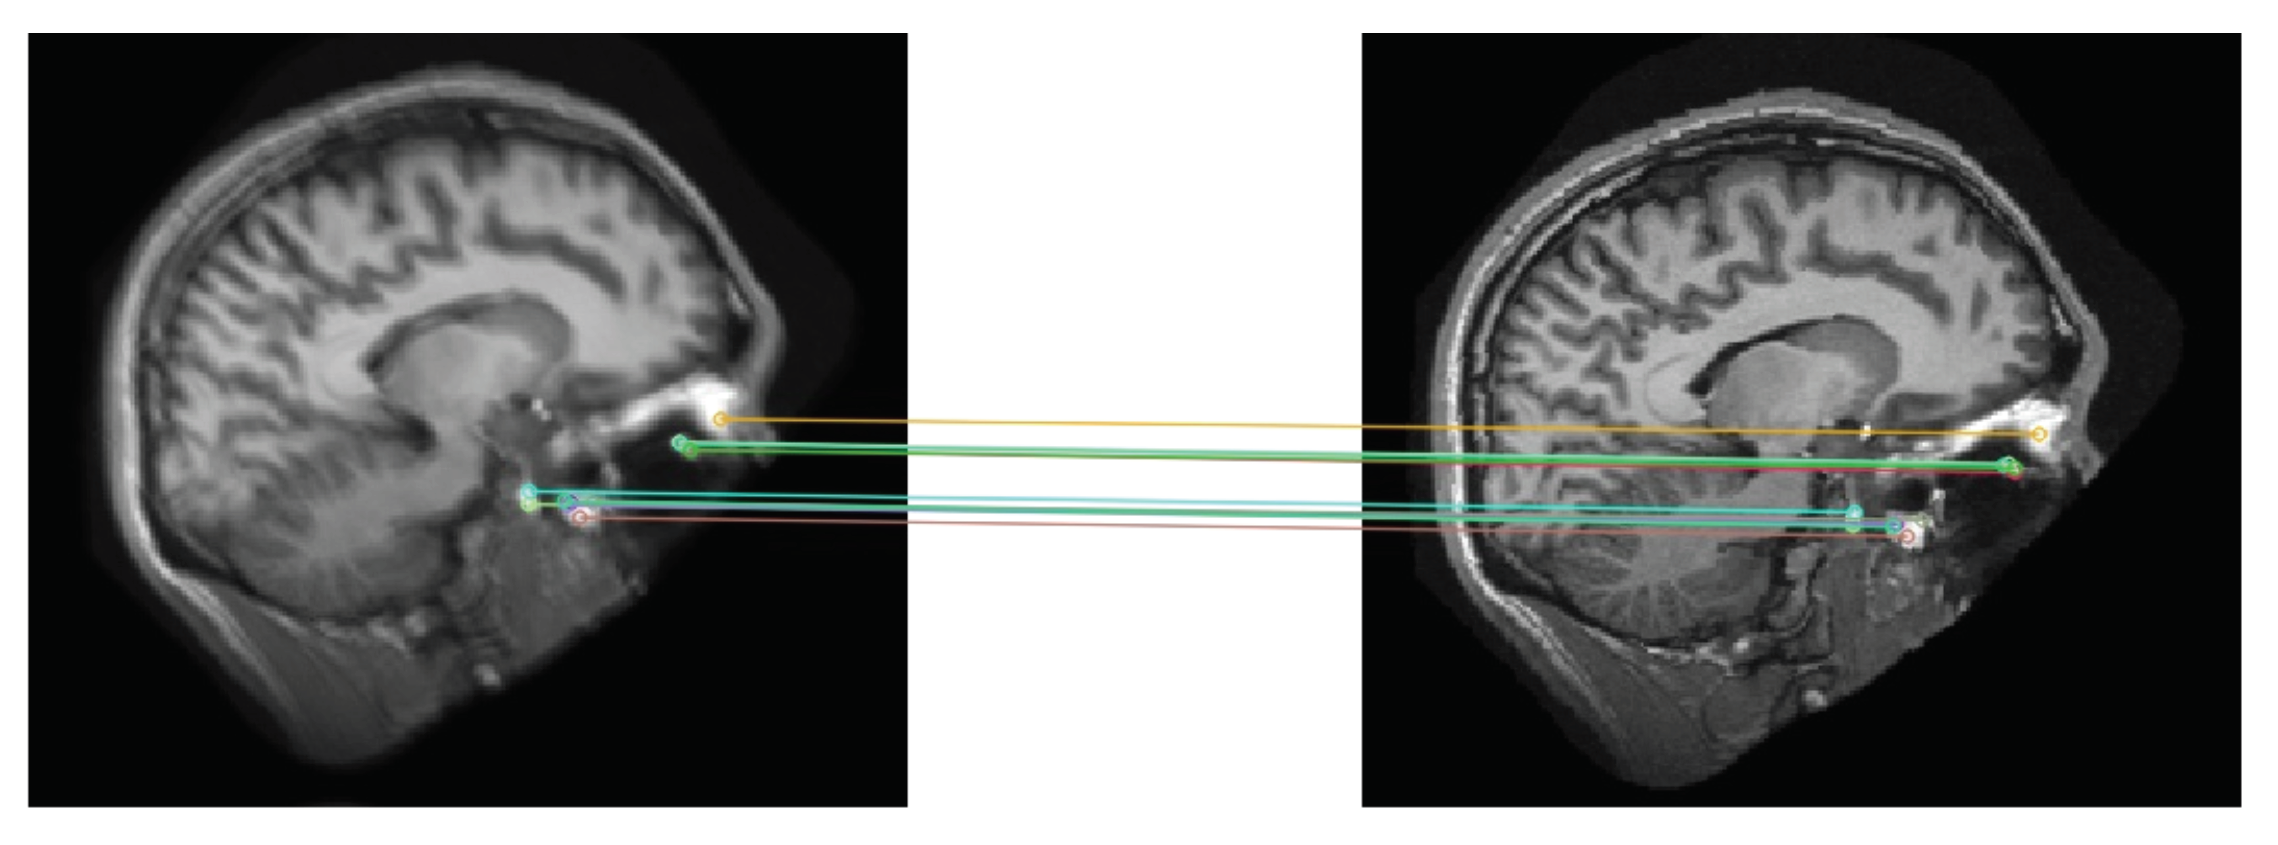

4.2.1. Generating Synthetic Artifact-Free Data